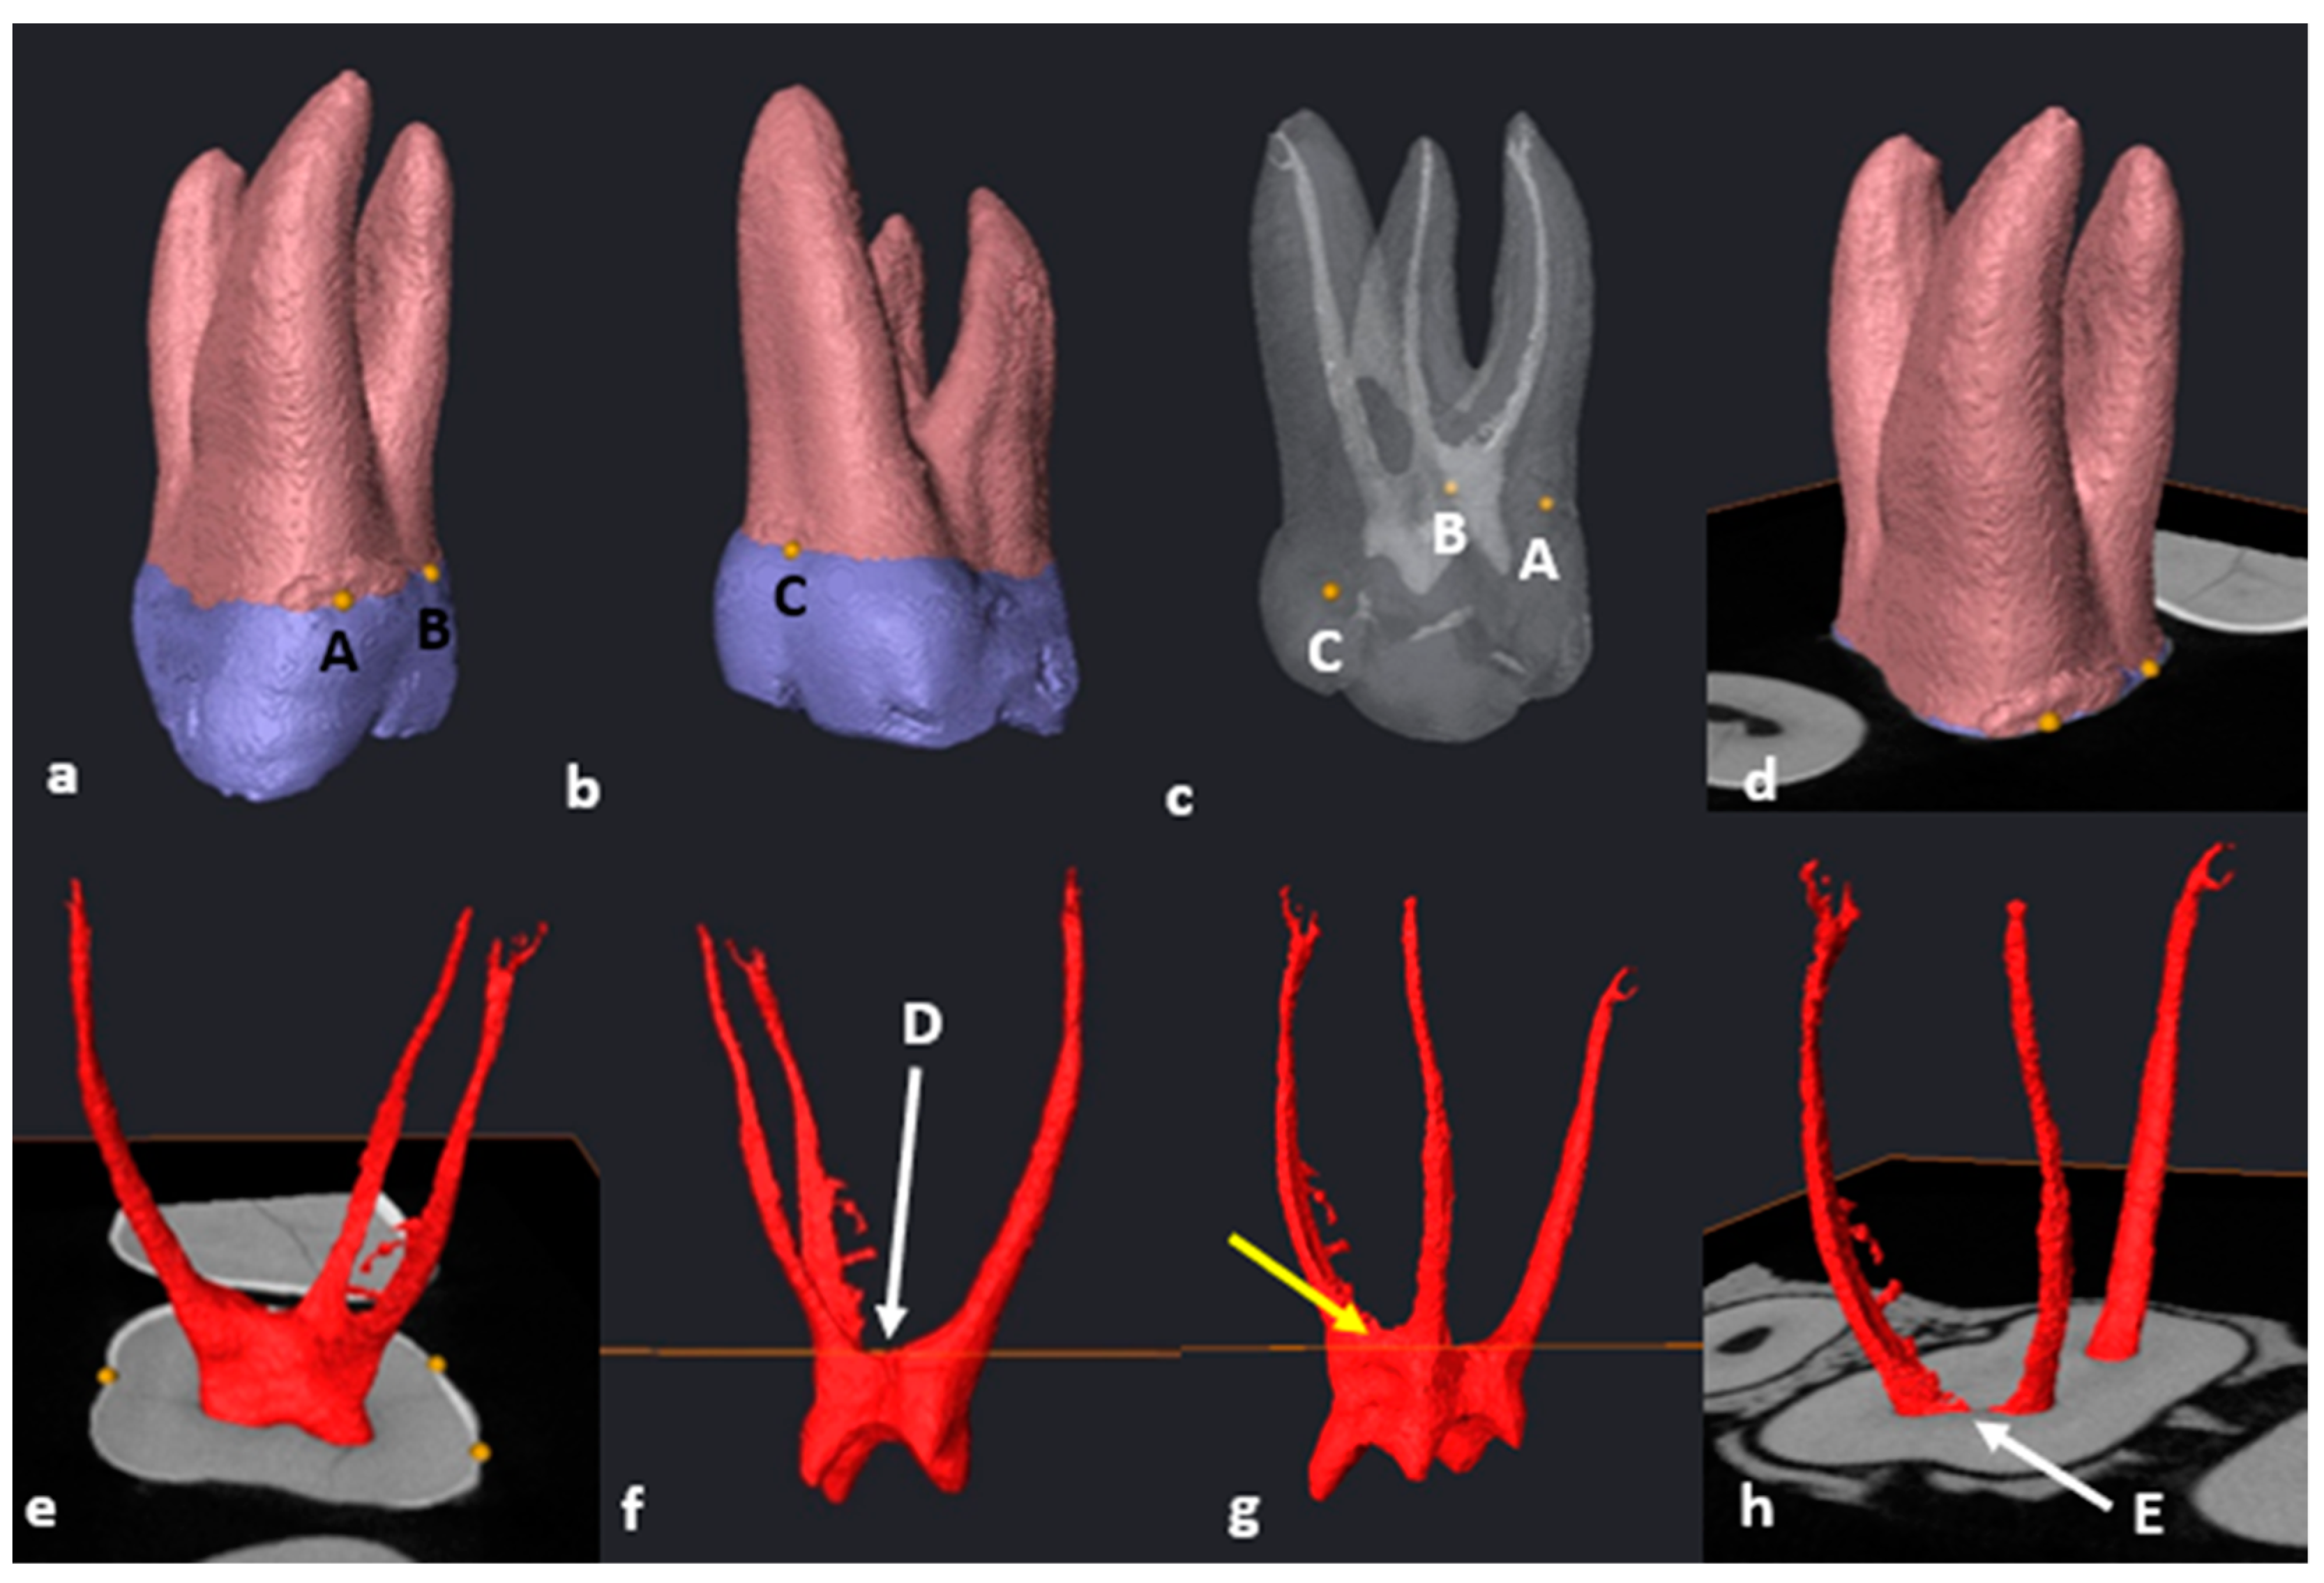

2.6. Segmentation and Landmark Identification

3.5. Fused Roots

3.6. C-Shaped Canals